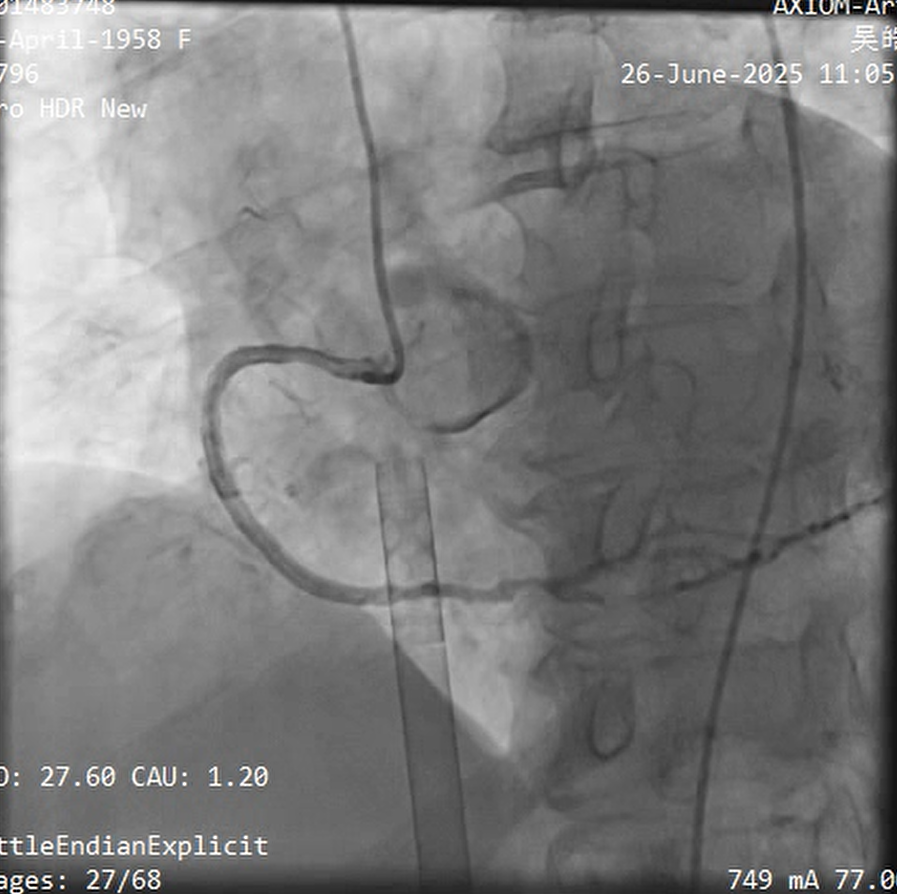

Relevant Catheterization Findings

30% stenosis in LMT; 100% stenosis in LCX£»99% stenosis with calcification in the LAD£»99% stenosis in the RCA¡£

LAD:

Neither 0.8 ¡¿ 10 mm nor 1.25 ¡¿ 15 mm balloon could cross the mid LAD lesion; tactile feedback confirmed calcification;

Rotational atherectomy was initiated. However, the microcatheter could only be advanced to the mid segment of the LAD. The rotawire was then exchanged through the microcatheter;

1.25mm Bur£¬a distinct "breakthrough" sensation was felt as the rotablation burr crossed the mid LAD lesion;

During rotational atherectomy, transient coronary no-reflow occurred, accompanied by hypotension and bradycardia.;

The 2.0 ¡¿ 15 mm balloon successfully and smoothly crossed;

LAD 6-8, a 2.0 ¡¿ 24 mm DCB was deployed, followed by the implantation of a 2.75 ¡¿ 20 mm stent and a 3.5 ¡¿ 16 mm stent;